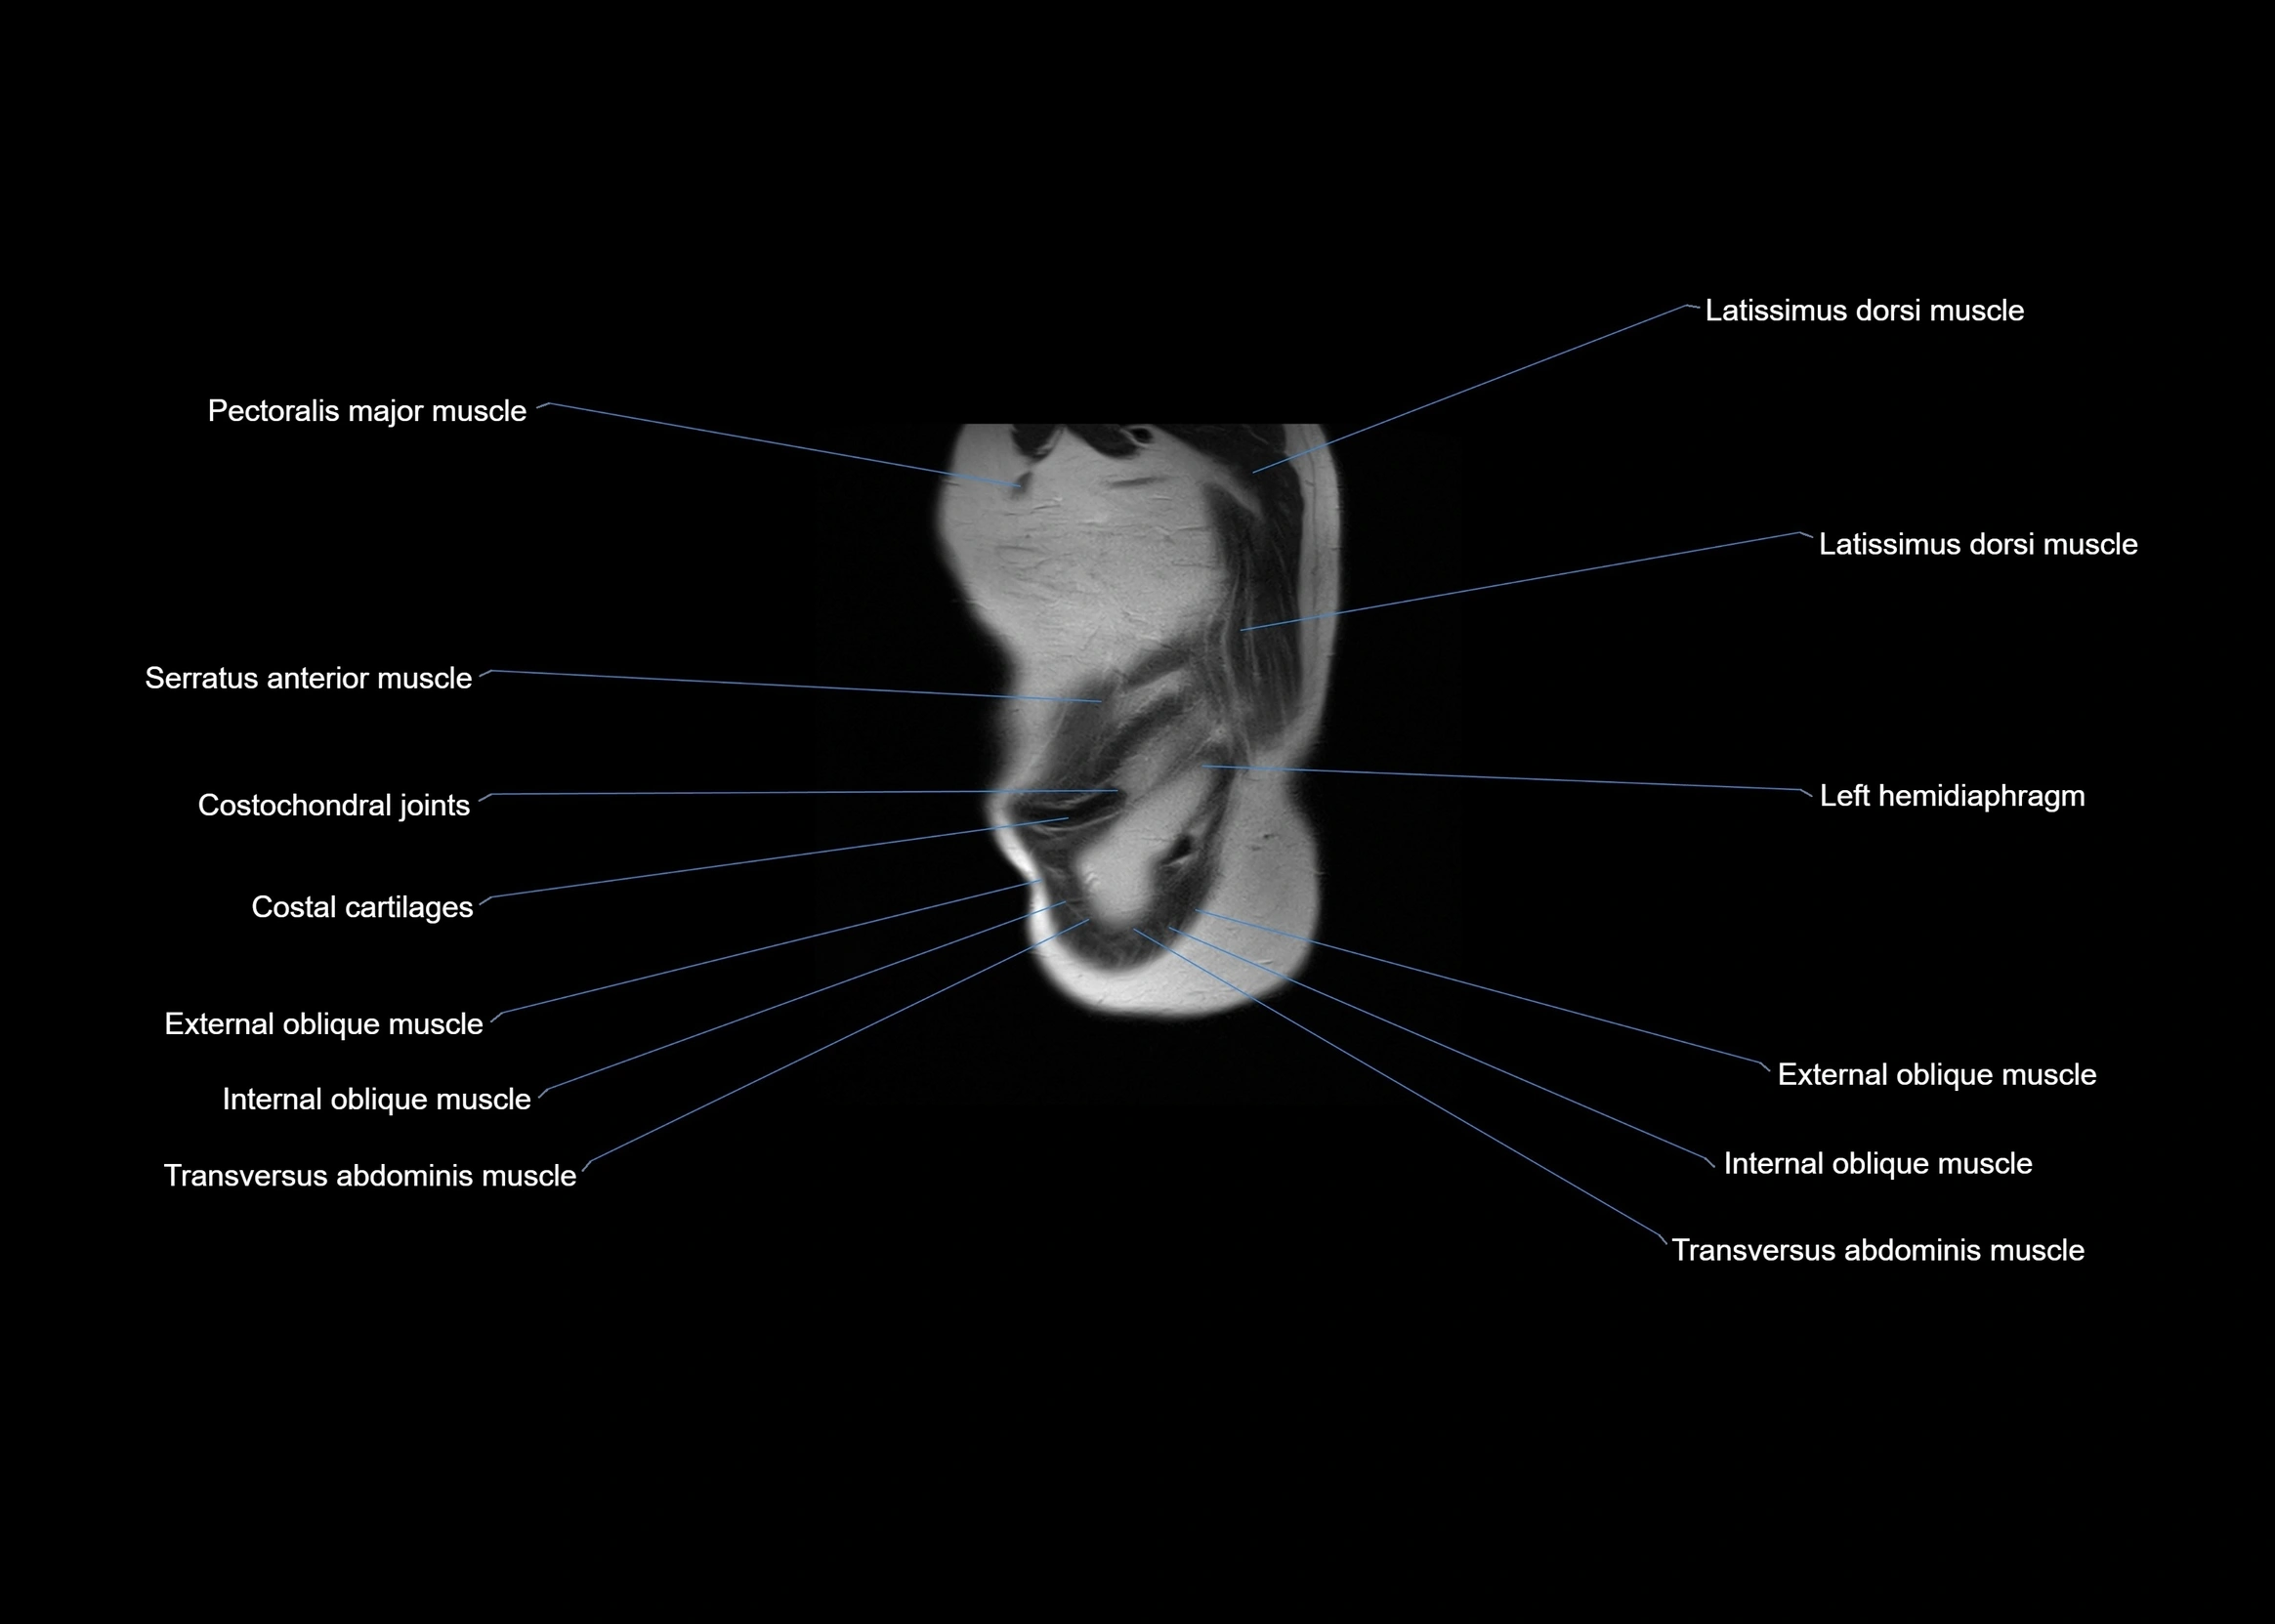

MRI images